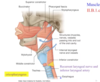

Identify the 3 muscules indicated in the photo. What is their function? What is their common posterior attachment?

Which is most superficiel?

Function: they constrict to propel structures down towards the esophagus; involved in swallowing & phonation

Attached Posterioly to pharyngeal raphe

Open anteriorly

inferior is most superficial